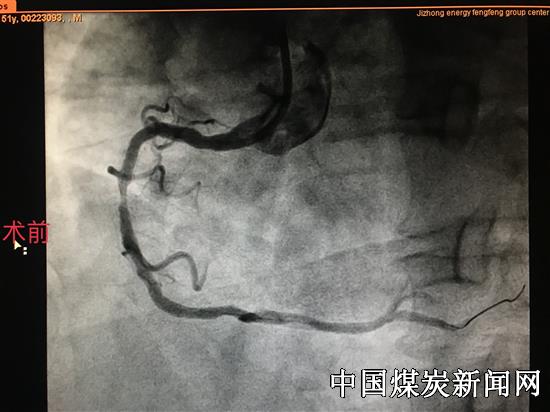

【本网讯】近日,冀中能源华北医疗健康产业集团峰峰总医院北院区心内科,独立成功为一名男性患者行药物球囊扩张治疗支架内再狭窄手术,手术过程顺利,术后患者恢复良好。此项新技术在本院区的独立完成,得到了业内知名专家和患者家属的充分肯定及认可!

患者男性,51岁,因冠心病于1年前在某医院行支架植入术,近日因反复胸闷、胸痛加重来我院心内科住院治疗。经科室副主任赵军峰及其主管医师会诊讨论后,决定为其行冠脉造影检查,检查结果显示患者右冠中段可见支架影,支架内狭窄。根据造影结果和病人自身情况该科医疗团队为其制定了科学的治疗方案,由该科副主任赵军峰及尹威、魏鹏辉医师为其行药物球囊扩张治疗支架内再狭窄手术。手术过程十分顺利,术后患者身体恢复良好,得到了患者及家属的高度认可和赞扬。此项技术不但解决了冠脉植入支架后再度出现血流不畅的诸多难题,同时,又大大提高了患者的生活质量。